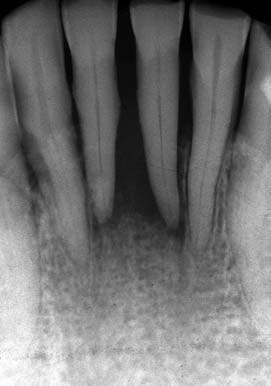

(図6)初診から33年経過(2008年1月7日)、71歳。咬耗は進んでいるが、骨植は堅固である

■症例:歯周疾患 (図1−6)

患者:71歳、女性。

著者が大学院学生時代からの長い付き合い(33年)の患者である。Sweetが大好物で、脂質異常症と高血圧症があるため、Sugar controlを常々指導するが、なかなか習慣は変えられないようである。長年、編み物教室の教師をしており、現在も毎日出張稽古で飛び回っているようである。ハイヒールをはいて社交ダンスを2〜3時間平気でしたり、毎年海外旅行へ行かれたり、非常に活動的な患者である。一時間かけて大阪から1回/月、定期的にSPTに努めてくれている。